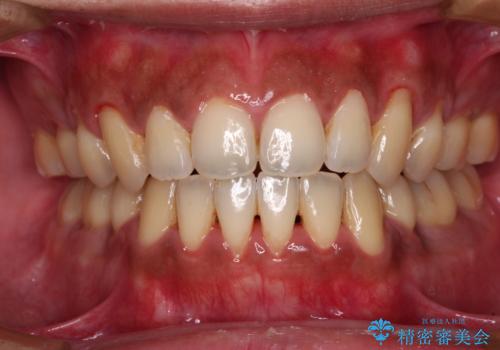

- 前歯のでこぼこと乳歯が残るほどの八重歯を気にして来院された患者様です。

非抜歯にてワイヤー矯正にて治療することとしました。(ただし、親知らずと乳歯は抜歯)

犬歯は歯根が太く長いため、移動には時間を要します。しかし、犬歯は機能面から考えて残すことを選択したいため、長期間をかけて治療を行うこととしました。

治療の度に歯列が改善していったため、長期間の治療も楽しく過ごしていいただき、満足のいく仕上がりとなりました。